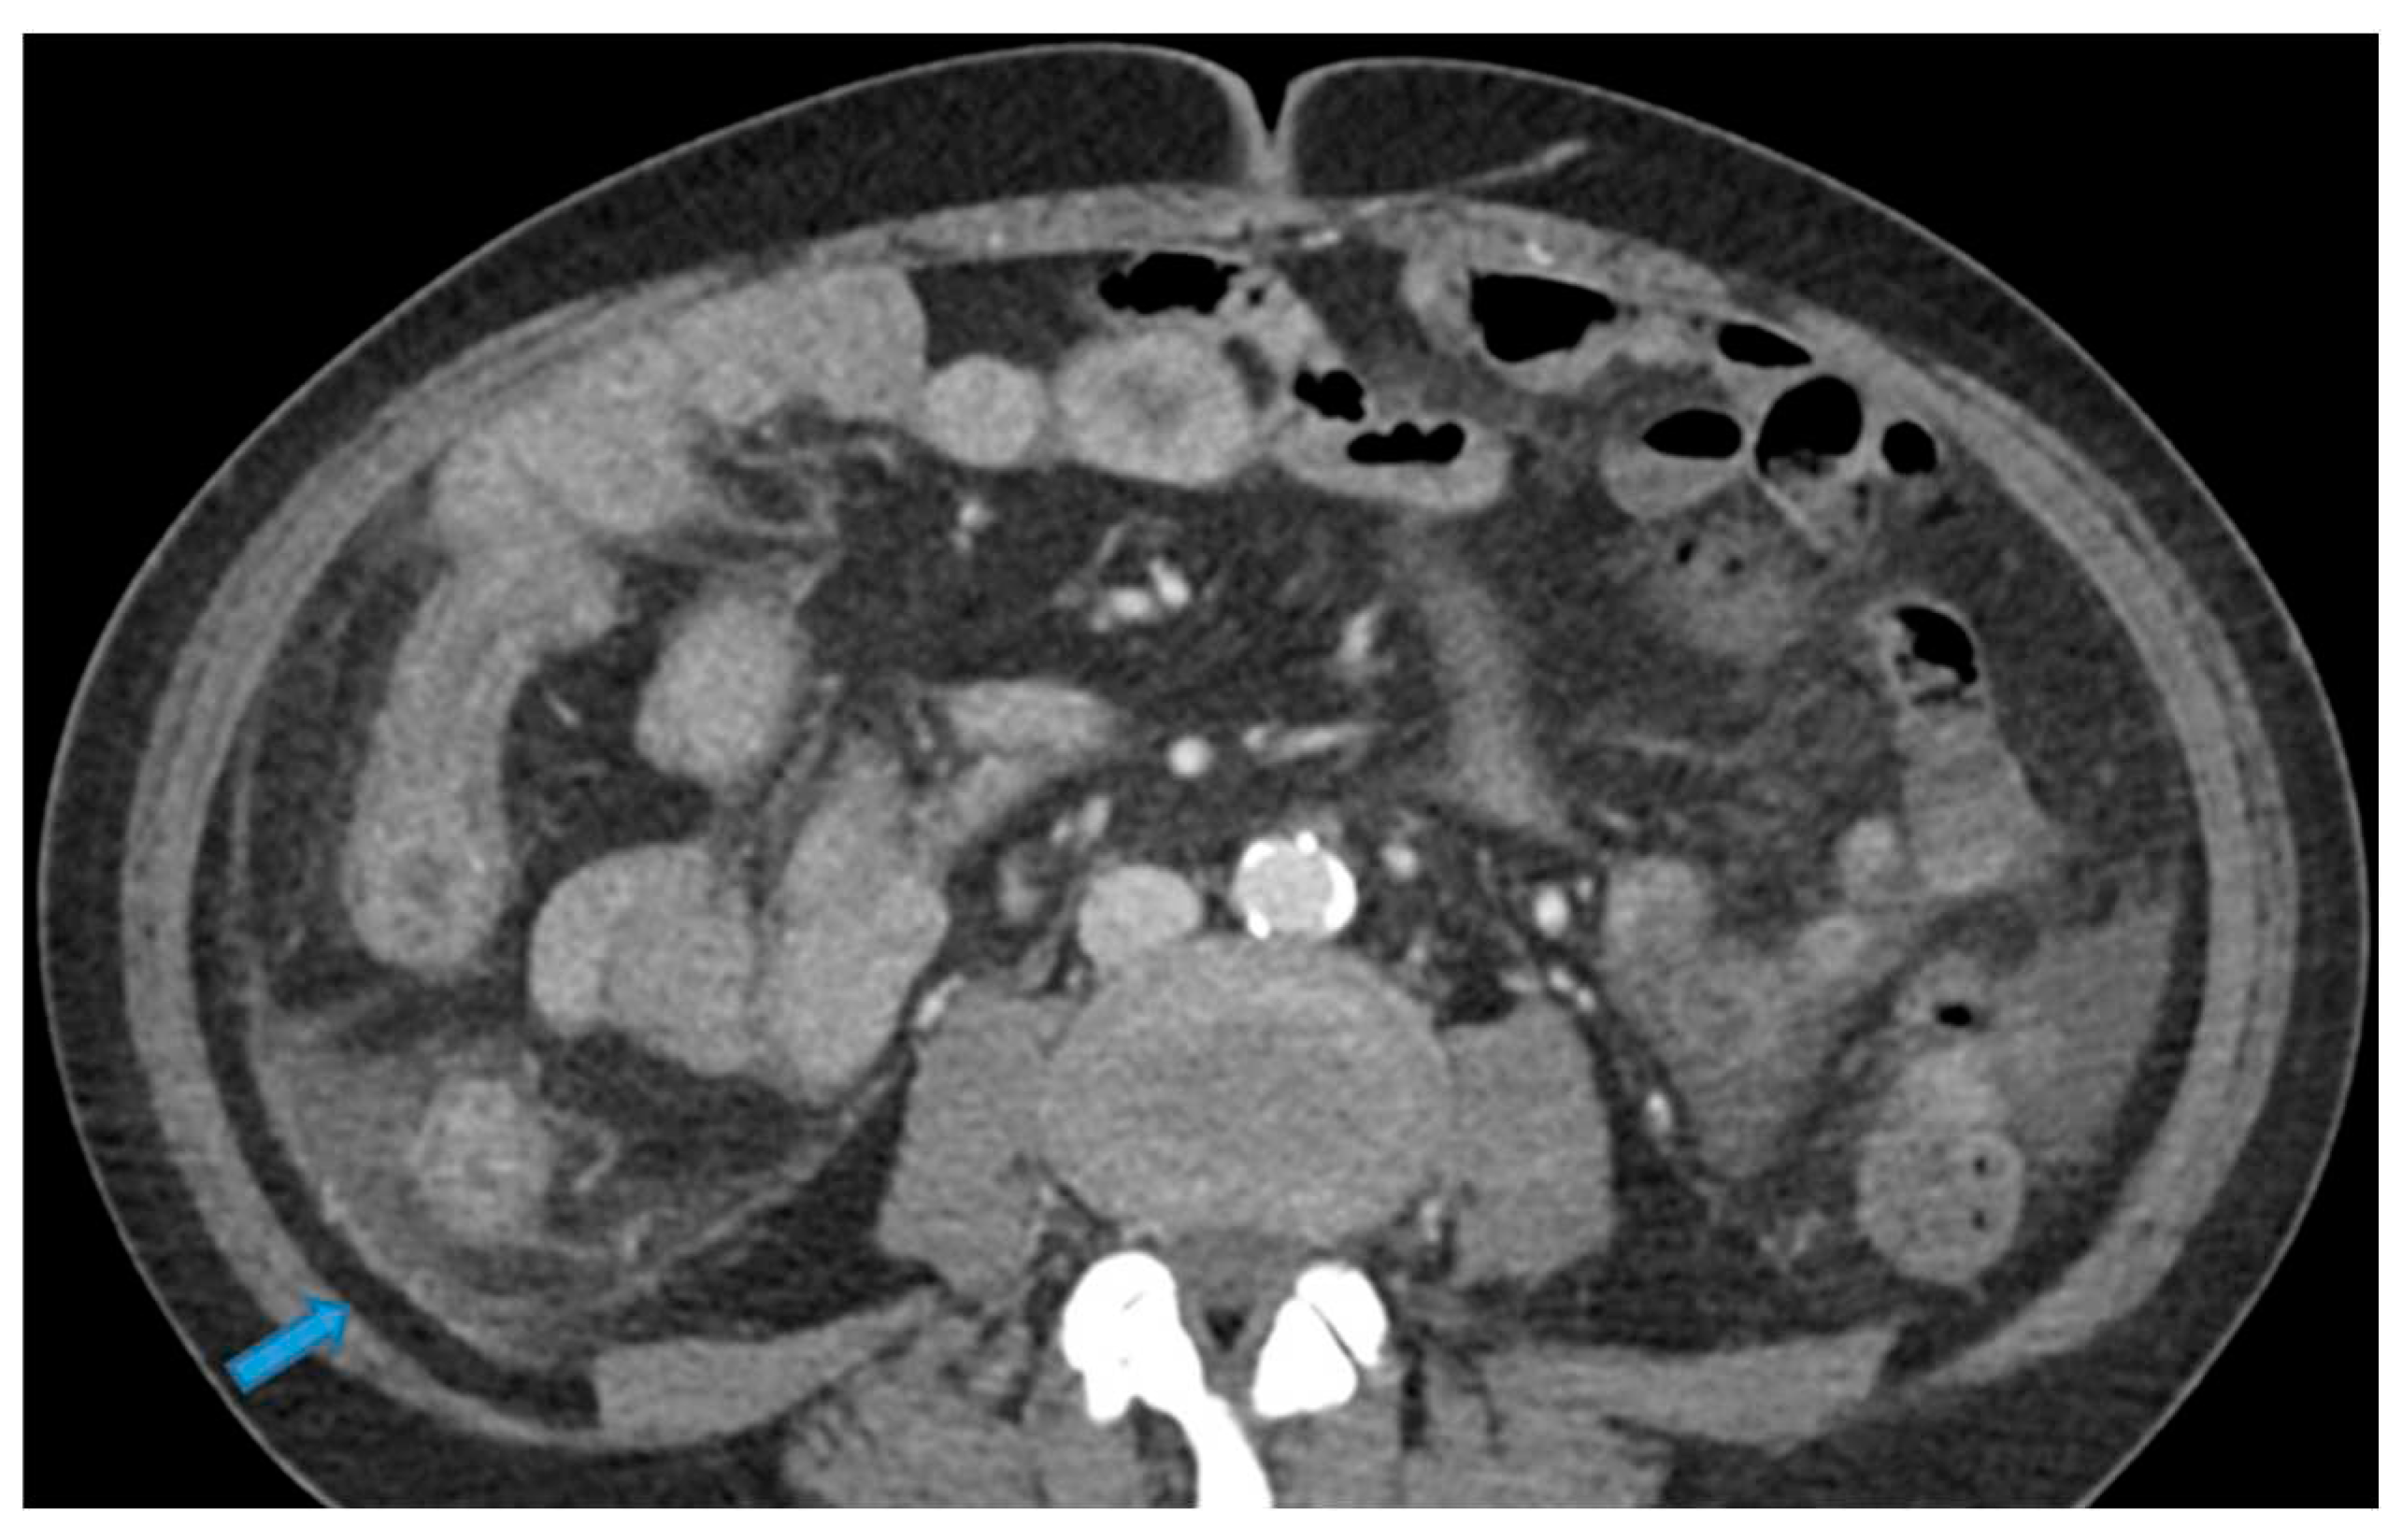

Figure 25.

Axial CE-CT. PC from colon adenocarcinoma: Involvement of the mesenteric leaves (note the nodular thickening and enhancement) that becomes more apparent with ascites.